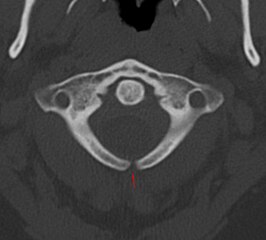

A posterior meningocele (/mɪˈnɪŋɡəˌsl/) or meningeal cyst (/mɪˈnɪniəl/) is the least common form of spina bifida. In this form, a single developmental defect allows the meninges to herniate between the vertebrae. As the nervous system remains undamaged, individuals with meningocele are unlikely to suffer long-term health problems, although cases of tethered cord have been reported. Causes of meningocele include teratoma and other tumors of the sacrococcyx and of the presacral space, and Currarino syndrome.

A meningocele may also form through dehiscences in the base of the skull. These may be classified by their localisation to occipital, frontoethmoidal, or nasal. Endonasal meningoceles lie at the roof of the nasal cavity and may be mistaken for a nasal polyp. They are treated surgically. Encephalomeningoceles are classified in the same way and also contain brain tissue.